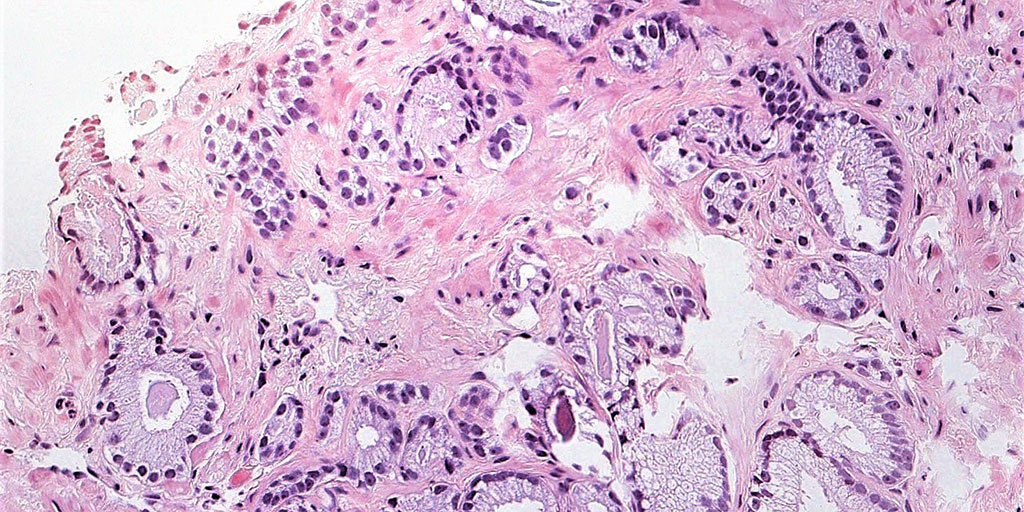

Immagine di tessuto mammario con colorazione immunoistochimica (Ki67), originale (sinistra) e normalizzata con STAINS (destra).